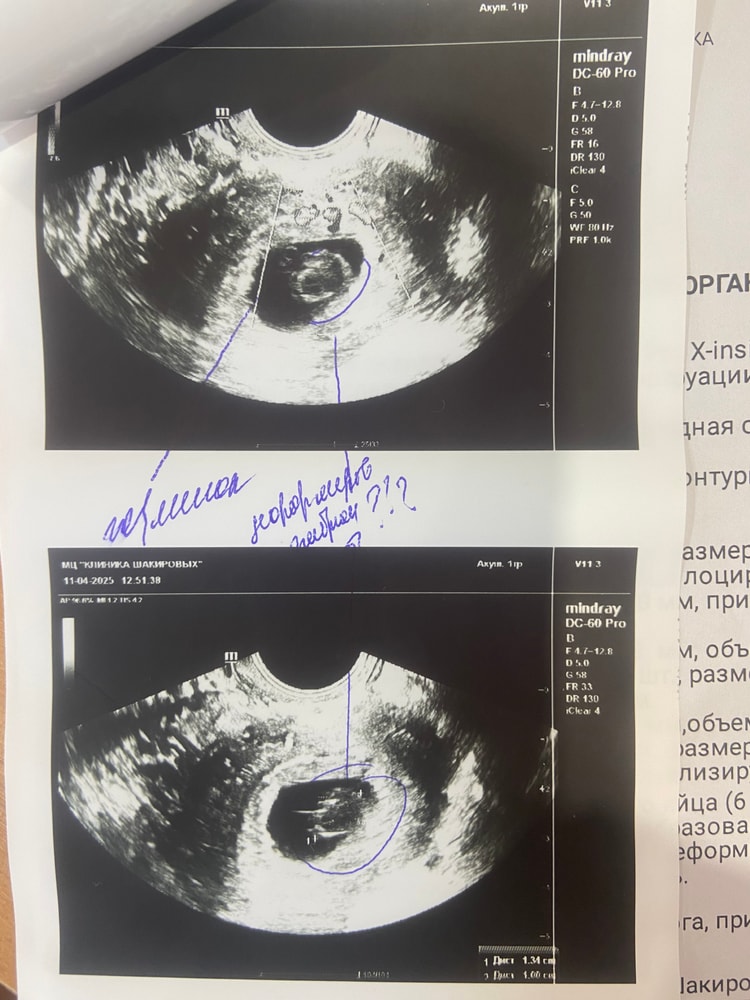

Марина, вот 7 апреля на первом узи у меня пя 12,98mm. И 11 марта я была на втором узи, я у узиста спросила, мне ставят срок 6 недель, это акушерские? Она мне ответила, что нет эмбриональные. Уже не знаю кого слушать и что делать

У меня в феврале была похожая история, ждала до 8-9 недель, но положили в больницу под наблюдение пролежала до ПЯ 28,8мм тм стал уменьшатся 1,8 мм а по первом узи 2,5мм потом 2 мм, подписала согласие на вакуум, так как самой стало видно что уже ждать бессмысленно, попробуйте уговорить врача положить под наблюдение так как сроки позволяют, хгч неинформативно уже, у меня отлично рос как обычная Б, но с первого узи ставили под вопросом, и так все 4 узи подтверждали анэмбрионию, не теряйте надежду но готовьтесь к худшему что бы быть готовой к любому исходу. Первое узи пя 9,3 мм жм 2,5мм 4459хгч Второе узи пя 21мм жм 2,5мм 8135хгч (в платной клинике ) Третье узи пя 25мм жм 2мм Четвертое узи пя 28,8 жм 1,8мм подтвердили Анэмбрионию подпись на вакуум хгч 18709 ( в стационаре )

Да, по месячным срок уже 7 недель у вас, и размер плодного яйца большой. Скорее врачи правы. скорее всего, беременность началась и по какой-то причине остановилось развитие эмбриона, такое случается часто. А ХГЧ растёт от плодного яйца, поэтому высокий. Но все равно всегда в динамике смотрят. Только не тяните, в течение недели переделать узи. И, если там все будет деградировать, то скорее на чистку нужно, чтобы восстановиться быстрее, и приступить к новой попытке

Я бы переделала узи, раз рост хгч такой шикарный и такие данные узи, действительно пугает что нашли еще что-то, КРОМЕ эмбриона и жм , +25мм пустое пя тоже вызывает сомнения

hsnvnst, жм есть

Диана Ноилес, да, я вижу. Жм вообще до 15мм пя появляется, а эмбрион ждут до 25мм. У вас уже срок поджимает(

Не хочу пугать, но учитывая что в плодном яйце врач видит что-то странное без кровотока и учитывая какой у вас быстрый рост ХГЧ при отсутствии эмбриона, то пузырный занос может быть вариантом тоже. В любом случае, идите к хорошему УЗИсту. Удачи!

Если сомневаетесь, сделайте через неделю, 1,5 ещё раз узи.. Может сердцебиение появится.. Хотя если деформированный эмбрион... (1ый раз о таком слышу если честно), Хотя тут не знаешь что вам посоветовать... Наверное всё таки слушать врачей.. Я бы через неделю сделала узи и там решала...